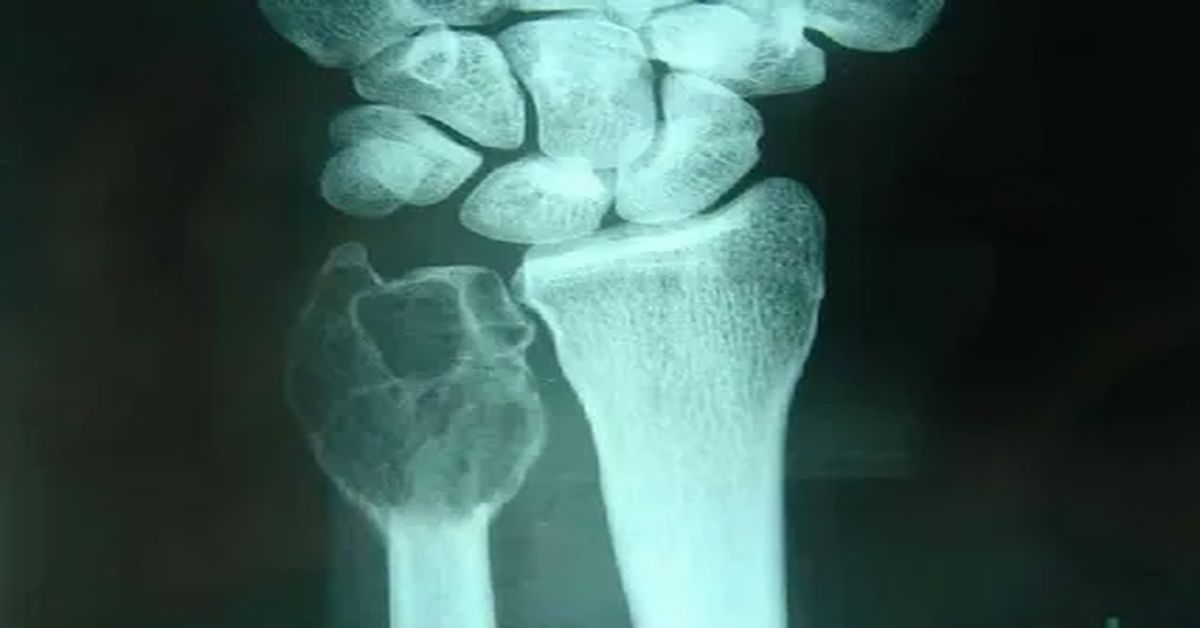

Tanıda ilk basamak genellikle röntgendir; ardından manyetik rezonans veya PET ile yayılım değerlendirilir.

Kesin tanı için uygun teknikle yapılan biyopsi şarttır. Erken başvuru hem kırık, deformite ve kalıcı fonksiyon kaybı riskini azaltır hem de tedavi seçeneklerini genişletir. Kitleyi zorlayarak masaj yapmak yerine, ortopedi deneyimi olan bir uzmana görünmek en güvenli yaklaşımdır.

Belirtiler genellikle sinsi başlar: gece artan ağrı ve açıklanamayan kırıklar dikkat çekicidir. Tanıda ilk adım röntgendir. Ardından MR/BT ile yerleşim ve yayılım değerlendirilir. Kesin tanı için uygun teknikle biyopsi yapılır ve patoloji sonucu tedaviyi belirler.